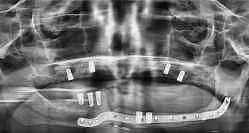

Zweizeitiger Knochenaufbau im Unterkieferseitenzahnbereich bei fortgeschrittener Atrophie nach Zahnverlust mit einem xenogenen1 Knochenersatzmaterial und nachfolgender „Guided surgery“ Implantation2: So erfolgte die orale Rehabilitation einer 33jährigen Patientin in der Klinik für Mund-, Kiefer-...